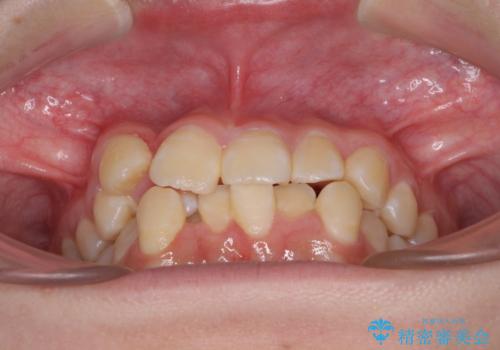

八重歯で正中が右にずれている ワイヤー装置での抜歯矯正で正中位置を改善

- 上下の八重歯と前歯のデコボコを気にして来院された患者様です。

右上の八重歯が特に著しく、上顎正中が右側にシフトしていました。

デコボコが強いため小臼歯4本を抜歯し、上顎正中を左側に移動させるために補助装置を使用して、ワイヤー装置にて矯正治療を行うこととしました。